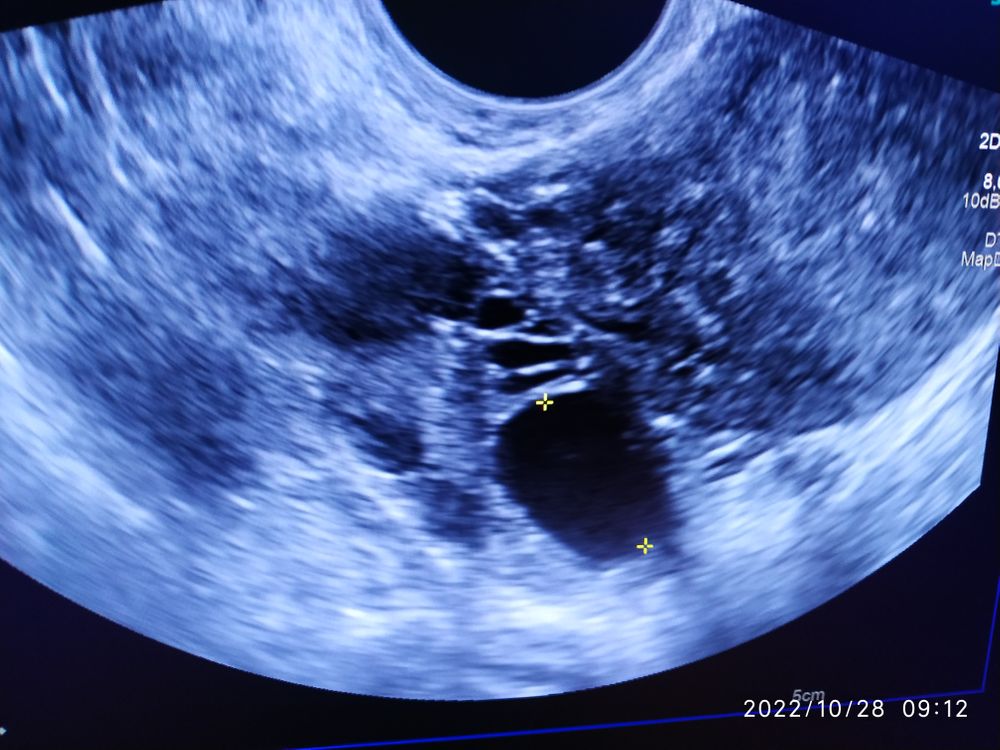

Фолликул 21 мм

Как думаете по форме ведь похож на намеревающий лопнуть фолликул? И ещё, можно ли где то на снимке увидеть с какой он стороны?

По поводу с какой стороны до вам на УЗИ должны были сказать. А форма и правда кривоватая))) может он сдуваться начинает?))

цикл какой у Вас? если это 23 дмц, то в динамике смотреть нужно, может фолликулярная киста.... Только врач при осмотре и УЗИ в динамике может сказать, нужны данные для ответов...